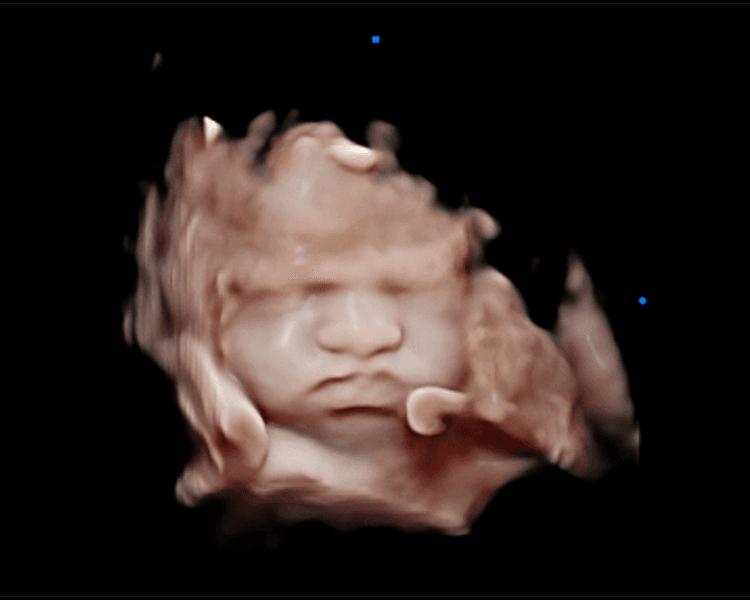

Ecografía Emocional 5D: Vive la Magia de Conocer a tu Bebé. En Ecolove ❤️, te invitamos a vivir una experiencia única y mágica con nuestra ecografía emocional 5D. Imagina ver a tu bebé en alta definición 3D y 5D, captando sus movimientos, gestos y hasta sus primeras sonrisas, todo con la calidad de una película de cine. 🎥 Es mucho más que una ecografía, es un momento lleno de amor, emoción y conexión. Un recuerdo eterno que podrás compartir con los que más quieres. 🤰🏻👨👩👦👦 ¡Reserva tu cita y deja que la magia del cine te acerque a tu bebé!